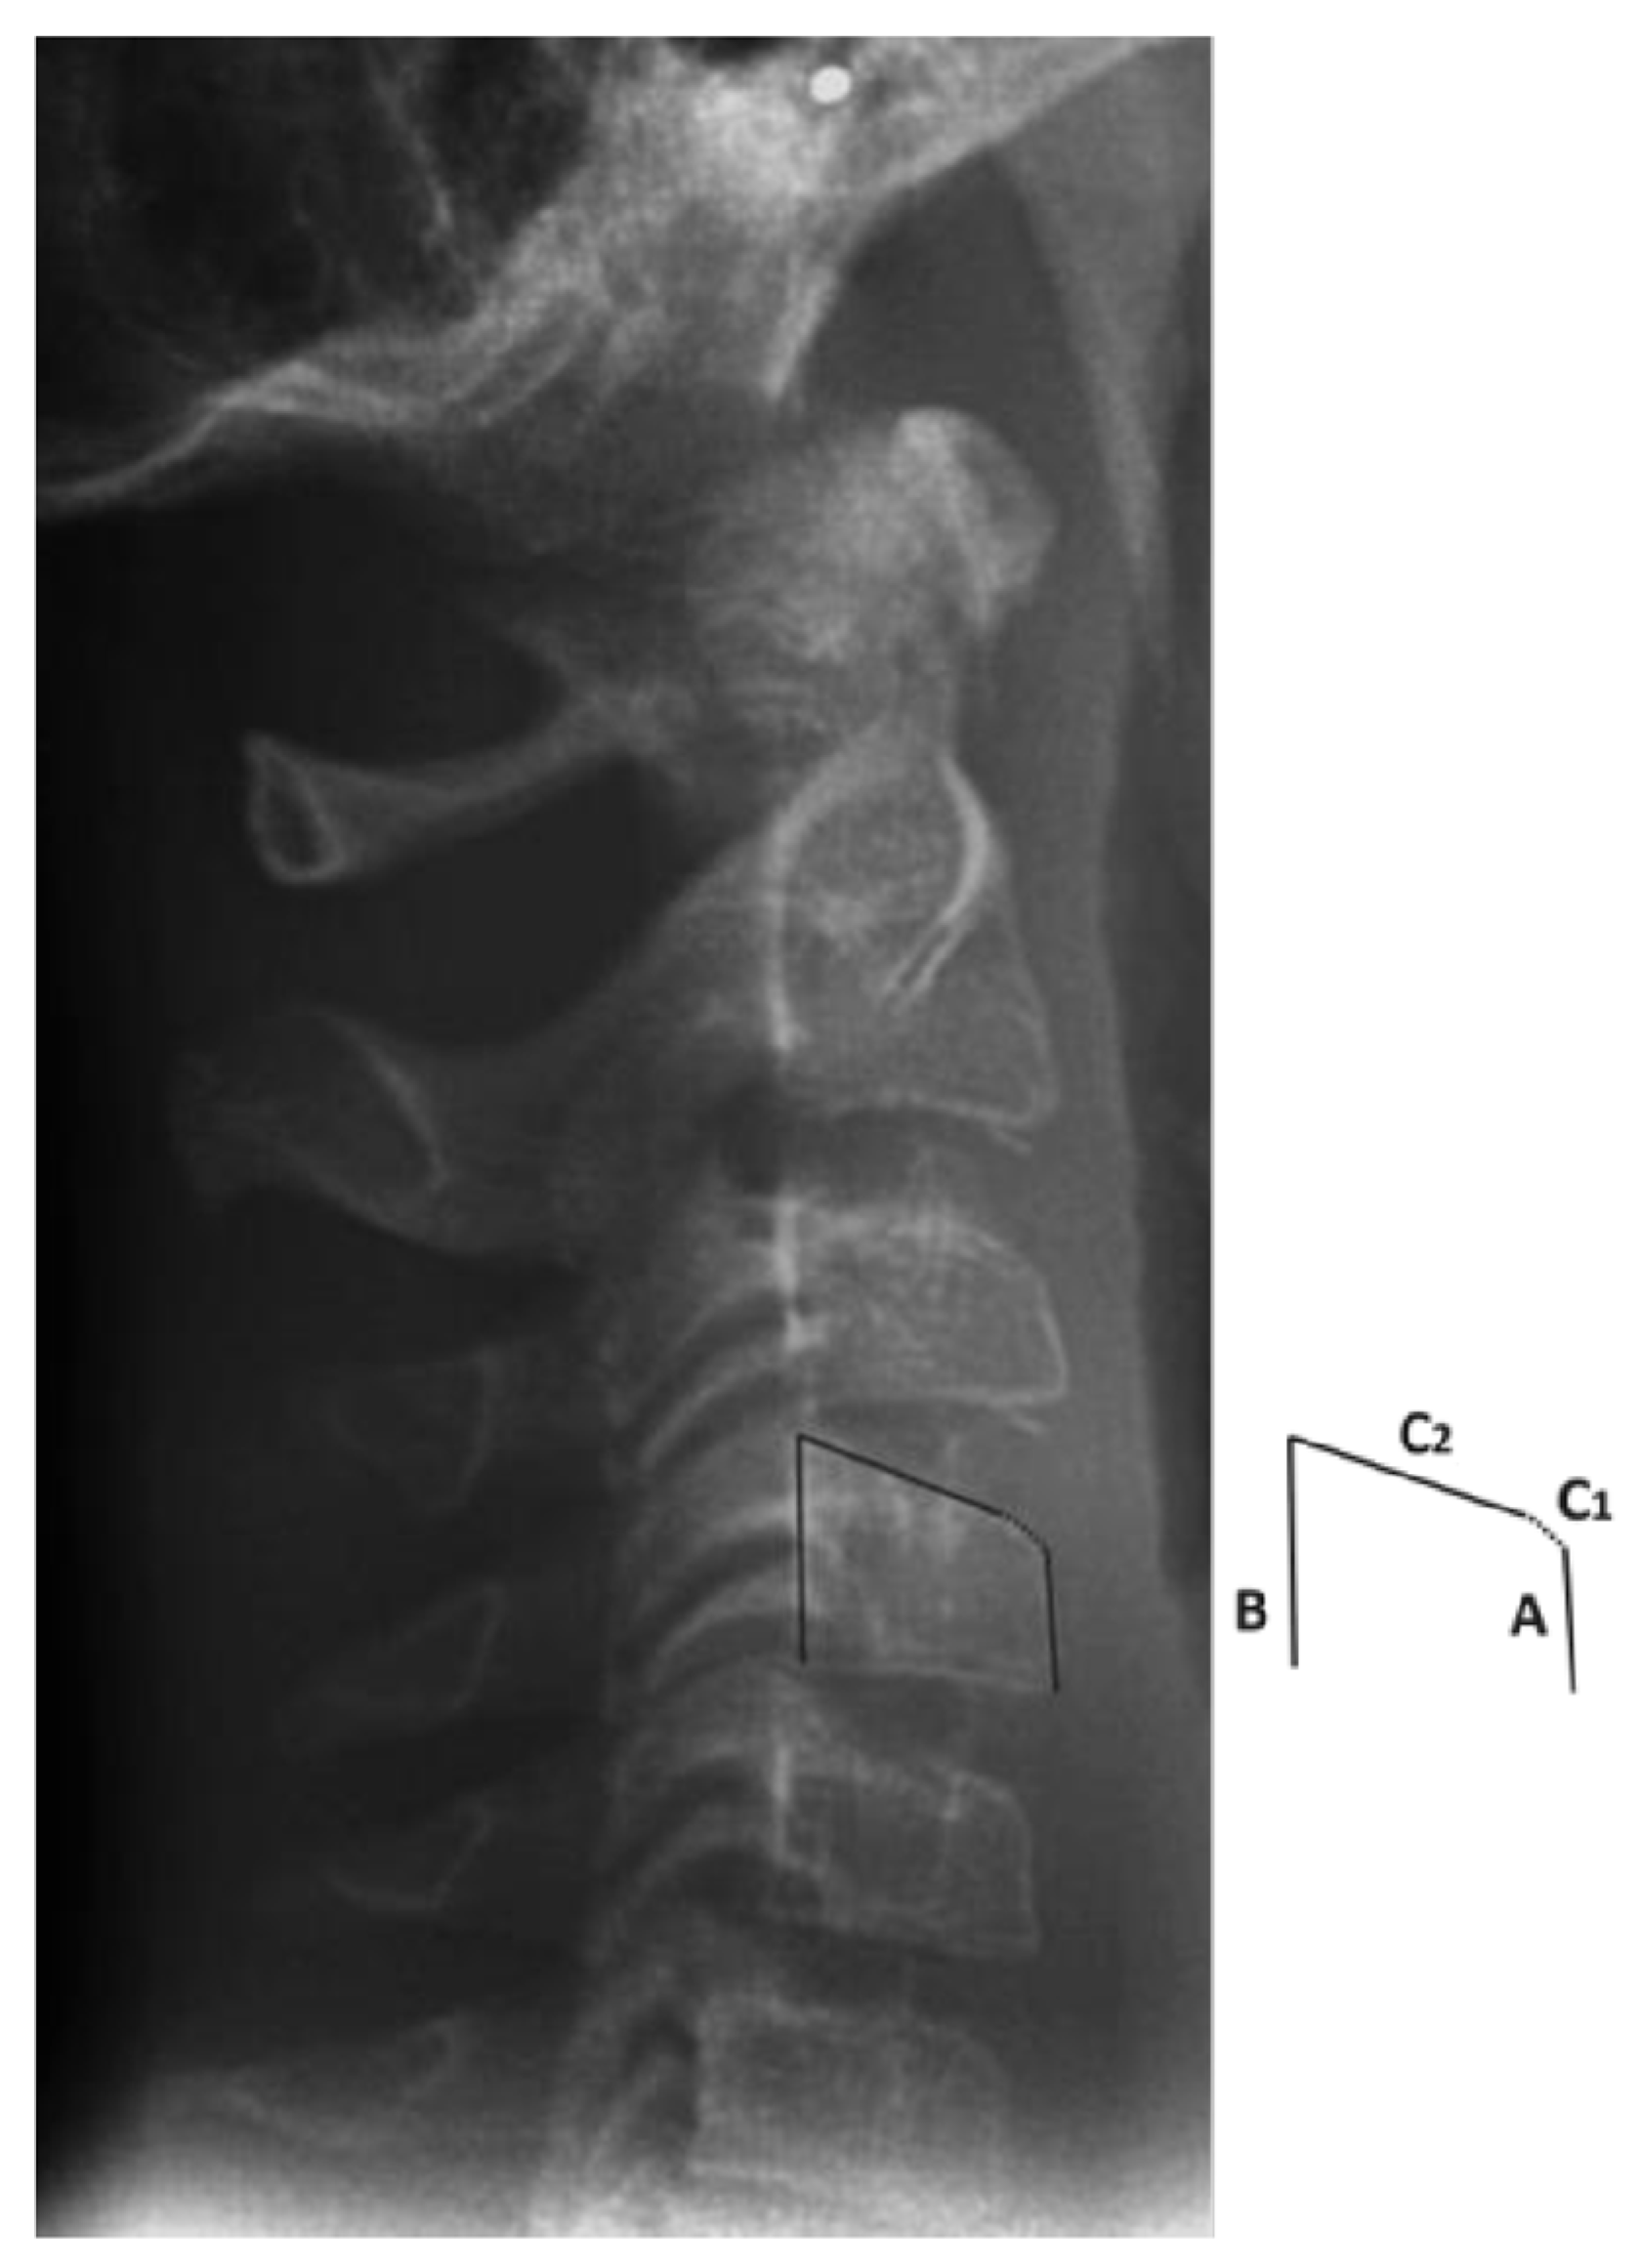

2. Materials and Methods